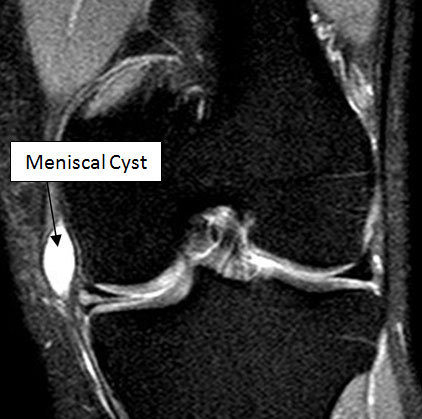

13. 반월상연골낭종(Meniscal cyst)은 무엇이고, 그 징후는 무엇인가?

반월상연골낭종(Meniscal cyst)은 반월판 파열 후에 반월상연골액의 분출로 인해 나타난다. 전형적으로 반월상 내부나 반월상낭 접합부의 반월판주변의 연부조직에서 발생한다. MRI가 반월상연골낭종을 진단하는 데 이학적 검진이나 관절경보다 더 민감하다. MRI 상에서 이러한 낭종은 T2 강조 영상에서 높은 신호 강도를 보인다. 이는 파열이 영상 상으로 보이지 않을 때조차 반월판 파열을 암시한다.

△ 반월상연골낭종 (Meniscal cyst) MRI

(http://www.kneesurgerymanchester.co.uk/knee-conditions/20-meniscal-cysts.html)